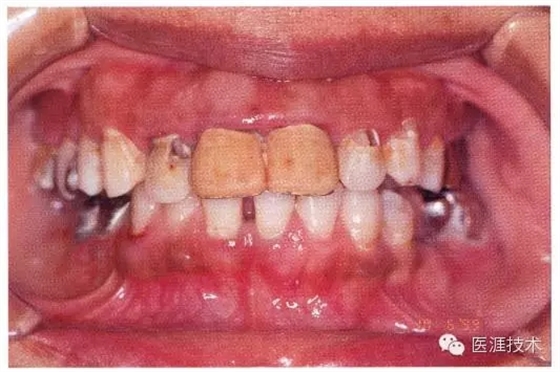

患有牙周病的牙周組織的臨床照片

640.webp (14).jpg

56歲牙周炎男性的臨床照片

640.webp (15).jpg

正在服用高血壓藥中的56歲男性。菌斑控制得不好。通過牙周探診,全頜有4~6mm的牙周袋,在X光片中可以看到全頜中度牙槽骨吸收,磨牙處一個(gè)地方是重度牙槽骨吸收。通過比較牙周病進(jìn)展?fàn)顟B(tài),邊緣部有大范圍浮腫(發(fā)紅、腫脹),和纖維性肥厚。這也可能是服用中的降壓藥的副作用導(dǎo)致的。因?yàn)檠例l、牙槽骨比較厚,牙齦呈架子狀。

55歲牙周炎男性的臨床照片

640.webp (16).jpg

55歲男性抽煙患者(1天20支、抽煙35年)。菌斑控制得不好。通過牙周探診,全頜有4~9mm的牙周袋,有1~3度的根分叉部病變。通過X光片觀察,上頜前牙中度牙槽骨吸收,其他地方有中度牙槽骨吸收。受吸煙影響,牙齦纖維性肥厚,呈紅黑色。牙齦幾乎沒有浮腫和發(fā)紅,所以這個(gè)病例是從外觀上無法預(yù)測(cè)病癥嚴(yán)重程度的病例。